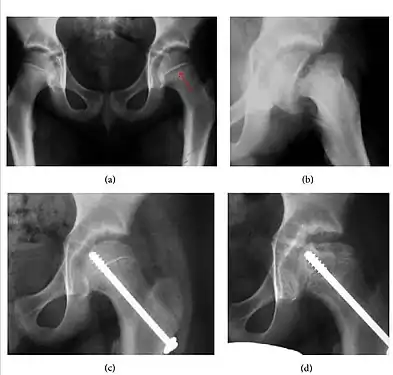

Slipped capital femoral epiphyses (SCFE) usually affect 11- to 14-year-old adolescents (Figure 4). Radiographs may show widening and irregularity of the physis and posterior inferior displacement of the capital femoral epiphysis. On the AP view Klein’s line, tangent to the lateral aspect of the femoral neck, does not intersect the femoral head indicating that it is displaced. SCFE may compromise the blood supply to the femoral head and cause avascular necrosis, mainly when there is instability between the fragments.[1]

- Figure 4: (a) X-ray of a 10-year-old child with left hip pain. It was considered normal at emergency despite the widening of the left physis (arrow). Two weeks later epiphysiolysis was evident (b). Despite appropriate surgical reduction (c) osteonecrosis developed and femoral head collapsed 1 month later (d).[1]